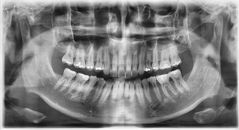

6000만 원 아끼려 튀르키예행…원정 시술 후 '치아 전부 발치'된 영국 男

오토바이 사고로 치아를 잃은 한 남성이 비용 부담을 줄이기 위해 해외에서 임플란트 시술을 받았다가 오히려 치아를 모두 잃게 된 사연이 공개됐다. 16일(현지시각) 영국 매체 미러(Mirror) 등 외신에 따르면 영국에 거주하는 배달원 존 덴튼(34)은 최근 튀르키예에서 치과 시술을 받은 뒤 심각한 부작용을 겪고 있다. 덴튼은 지난 2020년

서영은 인턴기자2026.04.19 18:28:00